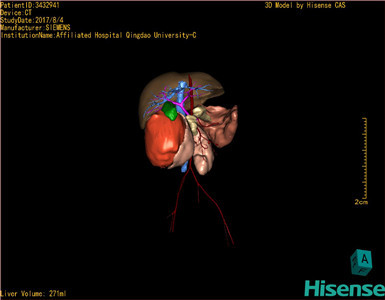

通过调节窗宽窗位调整CT序号,对肿瘤,肝实质,胆囊,下腔静脉,肿瘤,肝动脉、门静脉及肝静脉等进行三维重建;系统自动计算肿瘤体积和肝脏体积。

模拟手术操作,自动计算切除肿瘤体积。肝脏体积为271ml,通过术前模拟手术,精准判断手术可行性。

术前三维重建:

重建图片